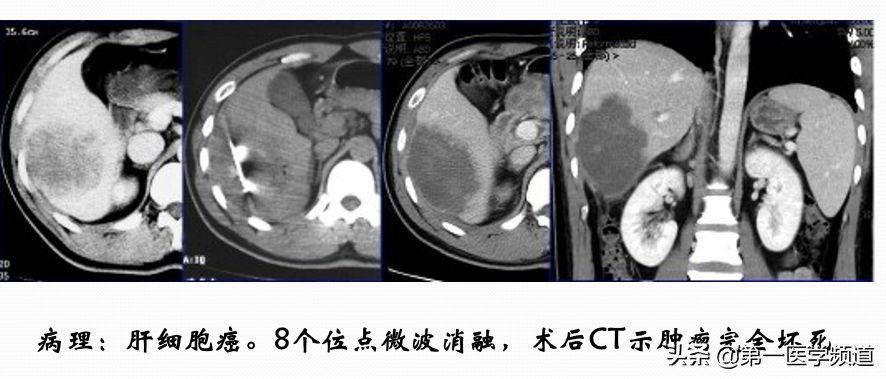

这是一个典型的微波治疗肝癌患者的案例。肝脏内比较大的肿块,接近5cm左右,我们通过8个位点做消融治疗,取得比较好的效果,术后肿瘤完全坏死。